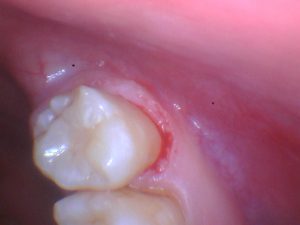

A new patient presented with root caries on the buccal and distal aspects of tooth #1 (Figure 1). His dentist of many years recommended an extraction, and the patient came to me for a second opinion. There is an opposing third molar, so this tooth is functional, although gaining access to restore the distal can be a challenge.

The tooth was prepared (Figure 2) and etched, followed by an application of Scotchbond Universal Adhesive (3M) and placement of ACTIVA BioACTIVE-RESTORATIVE. The ACTIVA BioACTIVE syringe has a bendable metal cannula, and this made it easy to access the distal of the third molar, which otherwise would have been much more difficult to treat. The material adapted well to the tooth and polished nicely, providing a very good result.